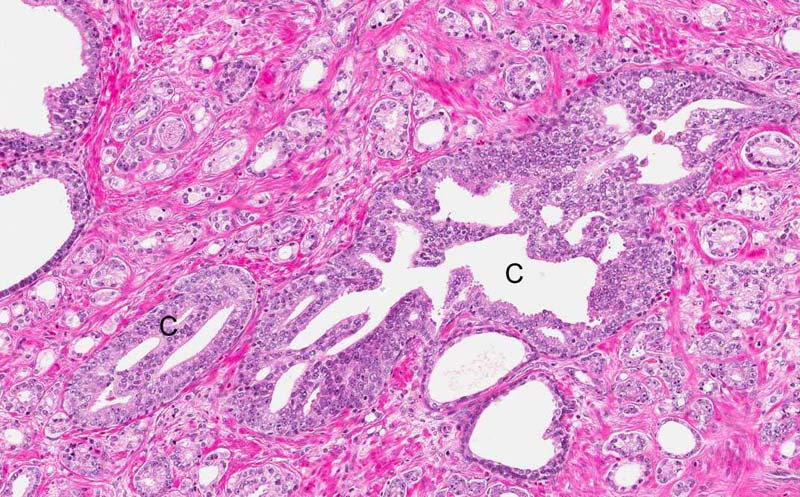

Area 1: In some of the tumor, a cribiform growth pattern is also present (C).

Hematoxylin & eosin

Area 2: Another area with cribiform area.

• In a minority of areas, the tumor demonstrate a cribiform growth pattern (Area 1).